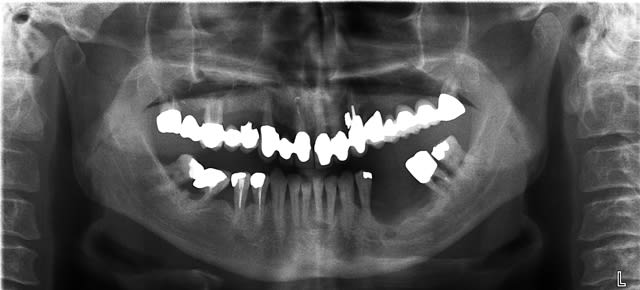

il est toujours facile de critiquer...mais il me semble que la pose de tes implants est un peu dyssymétrique à savoir que ton dernier implant droit sort en 44....extension risque d'être longue. il faut que ton extension arrive au moins à la première molaire de ton complet sup...pour ne pas le déstabiliser..

peut être vois-je mal..mais c'est l'impression que me donnes les photos.

c'est ne impression photo, je suis au niveau 45-46 juste en distal site ext 45...

je poste la pano et le reste cette sem, j'ai oublié le tout au cab

t'as des conseils pour ce cas là: ..........; le patient veut une solution long terme prévisible esthétique et surtout ne veut pas trop souffrir (greffes.....)